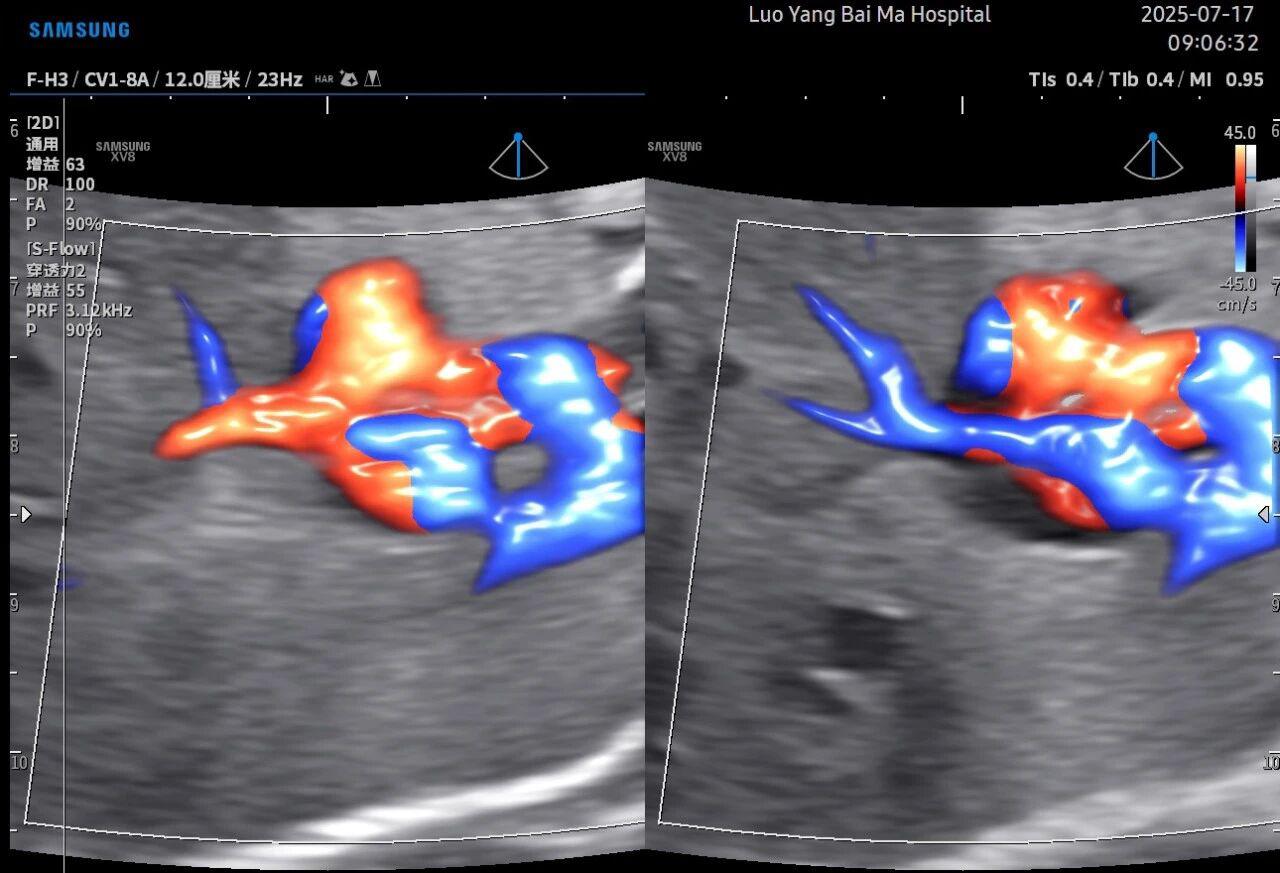

孕中期(通常在22-28周)的大排畸检查是整个孕期至关重要的环节之一。其目的在于系统地筛查胎儿是否存在结构性异常,如唇裂、脊柱裂、大脑、心脏、骨骼发育不良等问题。在这一关键检查中,5D智能彩超凭借其技术特性,展现出了显著的优势。

传统超声检查有时会因为胎儿体位、羊水量等因素的限制,导致某些部位观察不清。5D智能彩超技术能够实现对目标结构进行360°全方位、多切面的自由旋转观察。医生可以像“雕塑家”一样,从任意角度审视胎儿的解剖结构,尤其对于形态复杂的心脏、颅脑和脊柱等部位,这种能力可以极大弥补单一平面的局限性,帮助医生更全面地评估其发育状况。

这是5D技术的核心优势之一。系统内置了强大的智能化大数据分析功能和AI辅助诊断工具。例如,在进行胎儿颈项透明层(NT)测量、胎儿长骨(LB)测量等关键生物学指标评估时,5D智能系统可以自动识别解剖层面、智能勾勒测量范围并进行计算。这不仅大大缩短了检查时间,更重要的是,它通过标准化的智能算法减少了因人为操作可能产生的误差,使诊断结果更加客观、可靠。